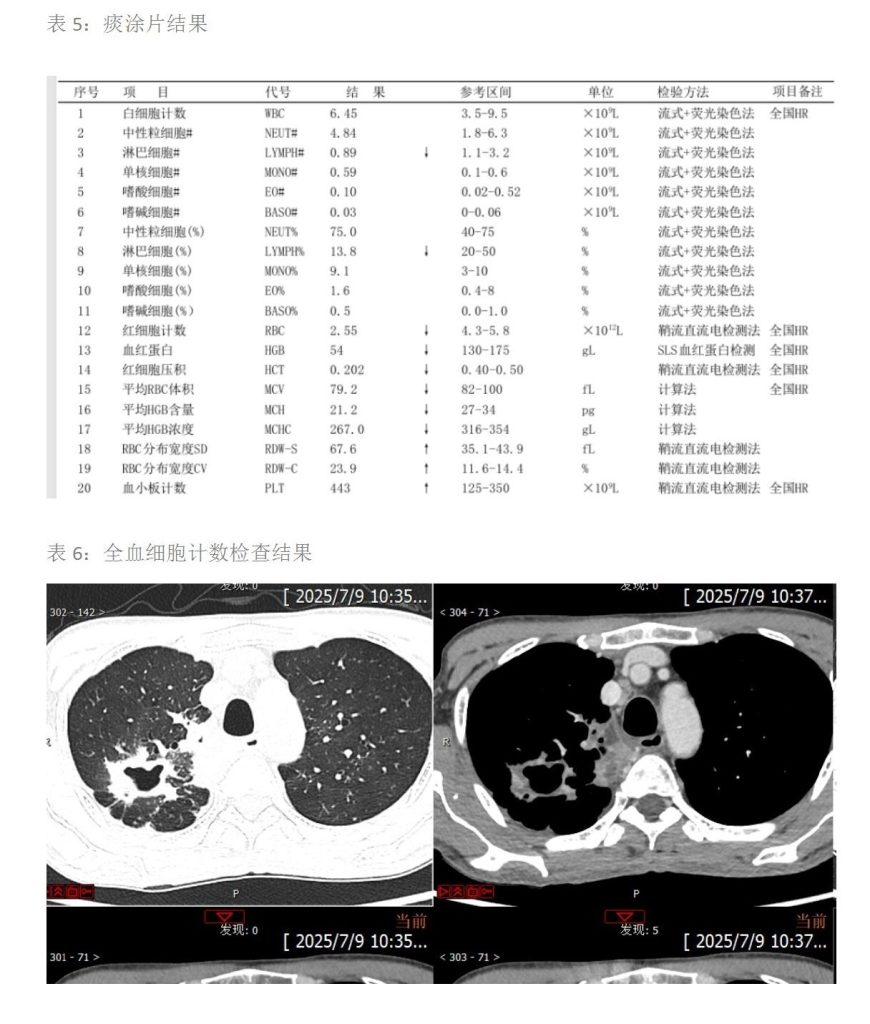

患者医学检验的呼吸道病原体 DNA、新冠病毒、HIV、TP、HCV 抗体和肿瘤标志物未见异常,乙肝两对半提示小三阳,痰涂片抗酸染色镜检抗酸杆菌呈现 2+;影像学胸部 CT 提示右肺上叶空洞形成,不除外结核。据患者体征畏寒,发热伴四肢乏力、困倦、纳差,偶有咳嗽表现,结合检验和影像的检查结果,考虑患者为感染性发热,结核分枝杆菌感染可能性大。

检验案例分析

该老年患者以发热,偶有咳嗽来就诊。30天前淋雨后开始出现症状,病程相对较长。入院查呼吸道病原体核酸,新冠病毒、HIV、TP、HCV-抗体都未见异常,血常规白细胞不高,重度贫血状态。影像学检查示:右肺上叶空洞形成,不除外结核。结合痰涂片抗酸染色发现抗酸杆菌2+,提示其可能为活动性肺结核,其传染性强。患者及时转到传染病专科医院进行诊治,我们继续对该病例进行追踪,最终患者痰液样本的结核杆菌DNA为阳性,遂明确诊断。